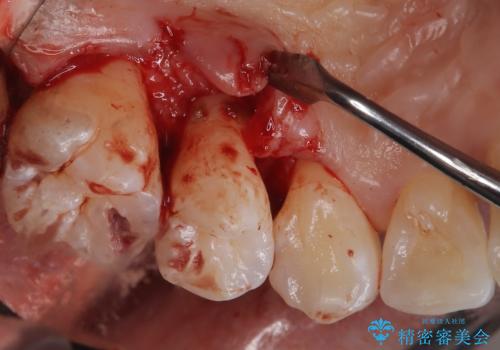

- 定期的にクリーニング(保険適応)に通って頂いている患者さんです。歯周ポケットが4ミリあったため歯茎を開いて歯石を除去するためにオープンフラップ術を行うことにしました。

歯周ポケットがそれほど深くない患者さんでしたが、いざ歯茎を開いてみるとそこにはたくさんの歯石がありました。もし歯周ポケットが4ミリだからと言って放置していれば数年後には、沢山の骨が無くなっていたことが予期出来ます。現段階で歯茎の下にある歯石を除去することにより骨が無くなることを予防する事が出来ました。